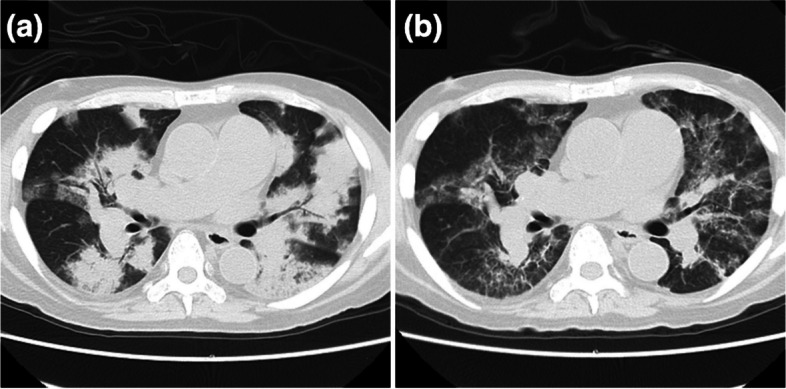

Case presentation: A 66-year-old man with pulmonary hypertension (PH) and glomerulonephritis was admitted with dyspnea. He had discontinued sildenafil prior to admission. Alveolar hemorrhage associated with AAV was suspected, and PE was performed. Soon after, he developed circulatory failure and hyperlactatemia. Echocardiography revealed right ventricular dilation, suggesting increased PVR. Inhaled nitric oxide (iNO) was administered, rapidly improving hyperlactatemia and oxygenation. The shock observed during PE was attributed to multiple factors, including the potential removal of sildenafil, which may have led to an increase in PVR.